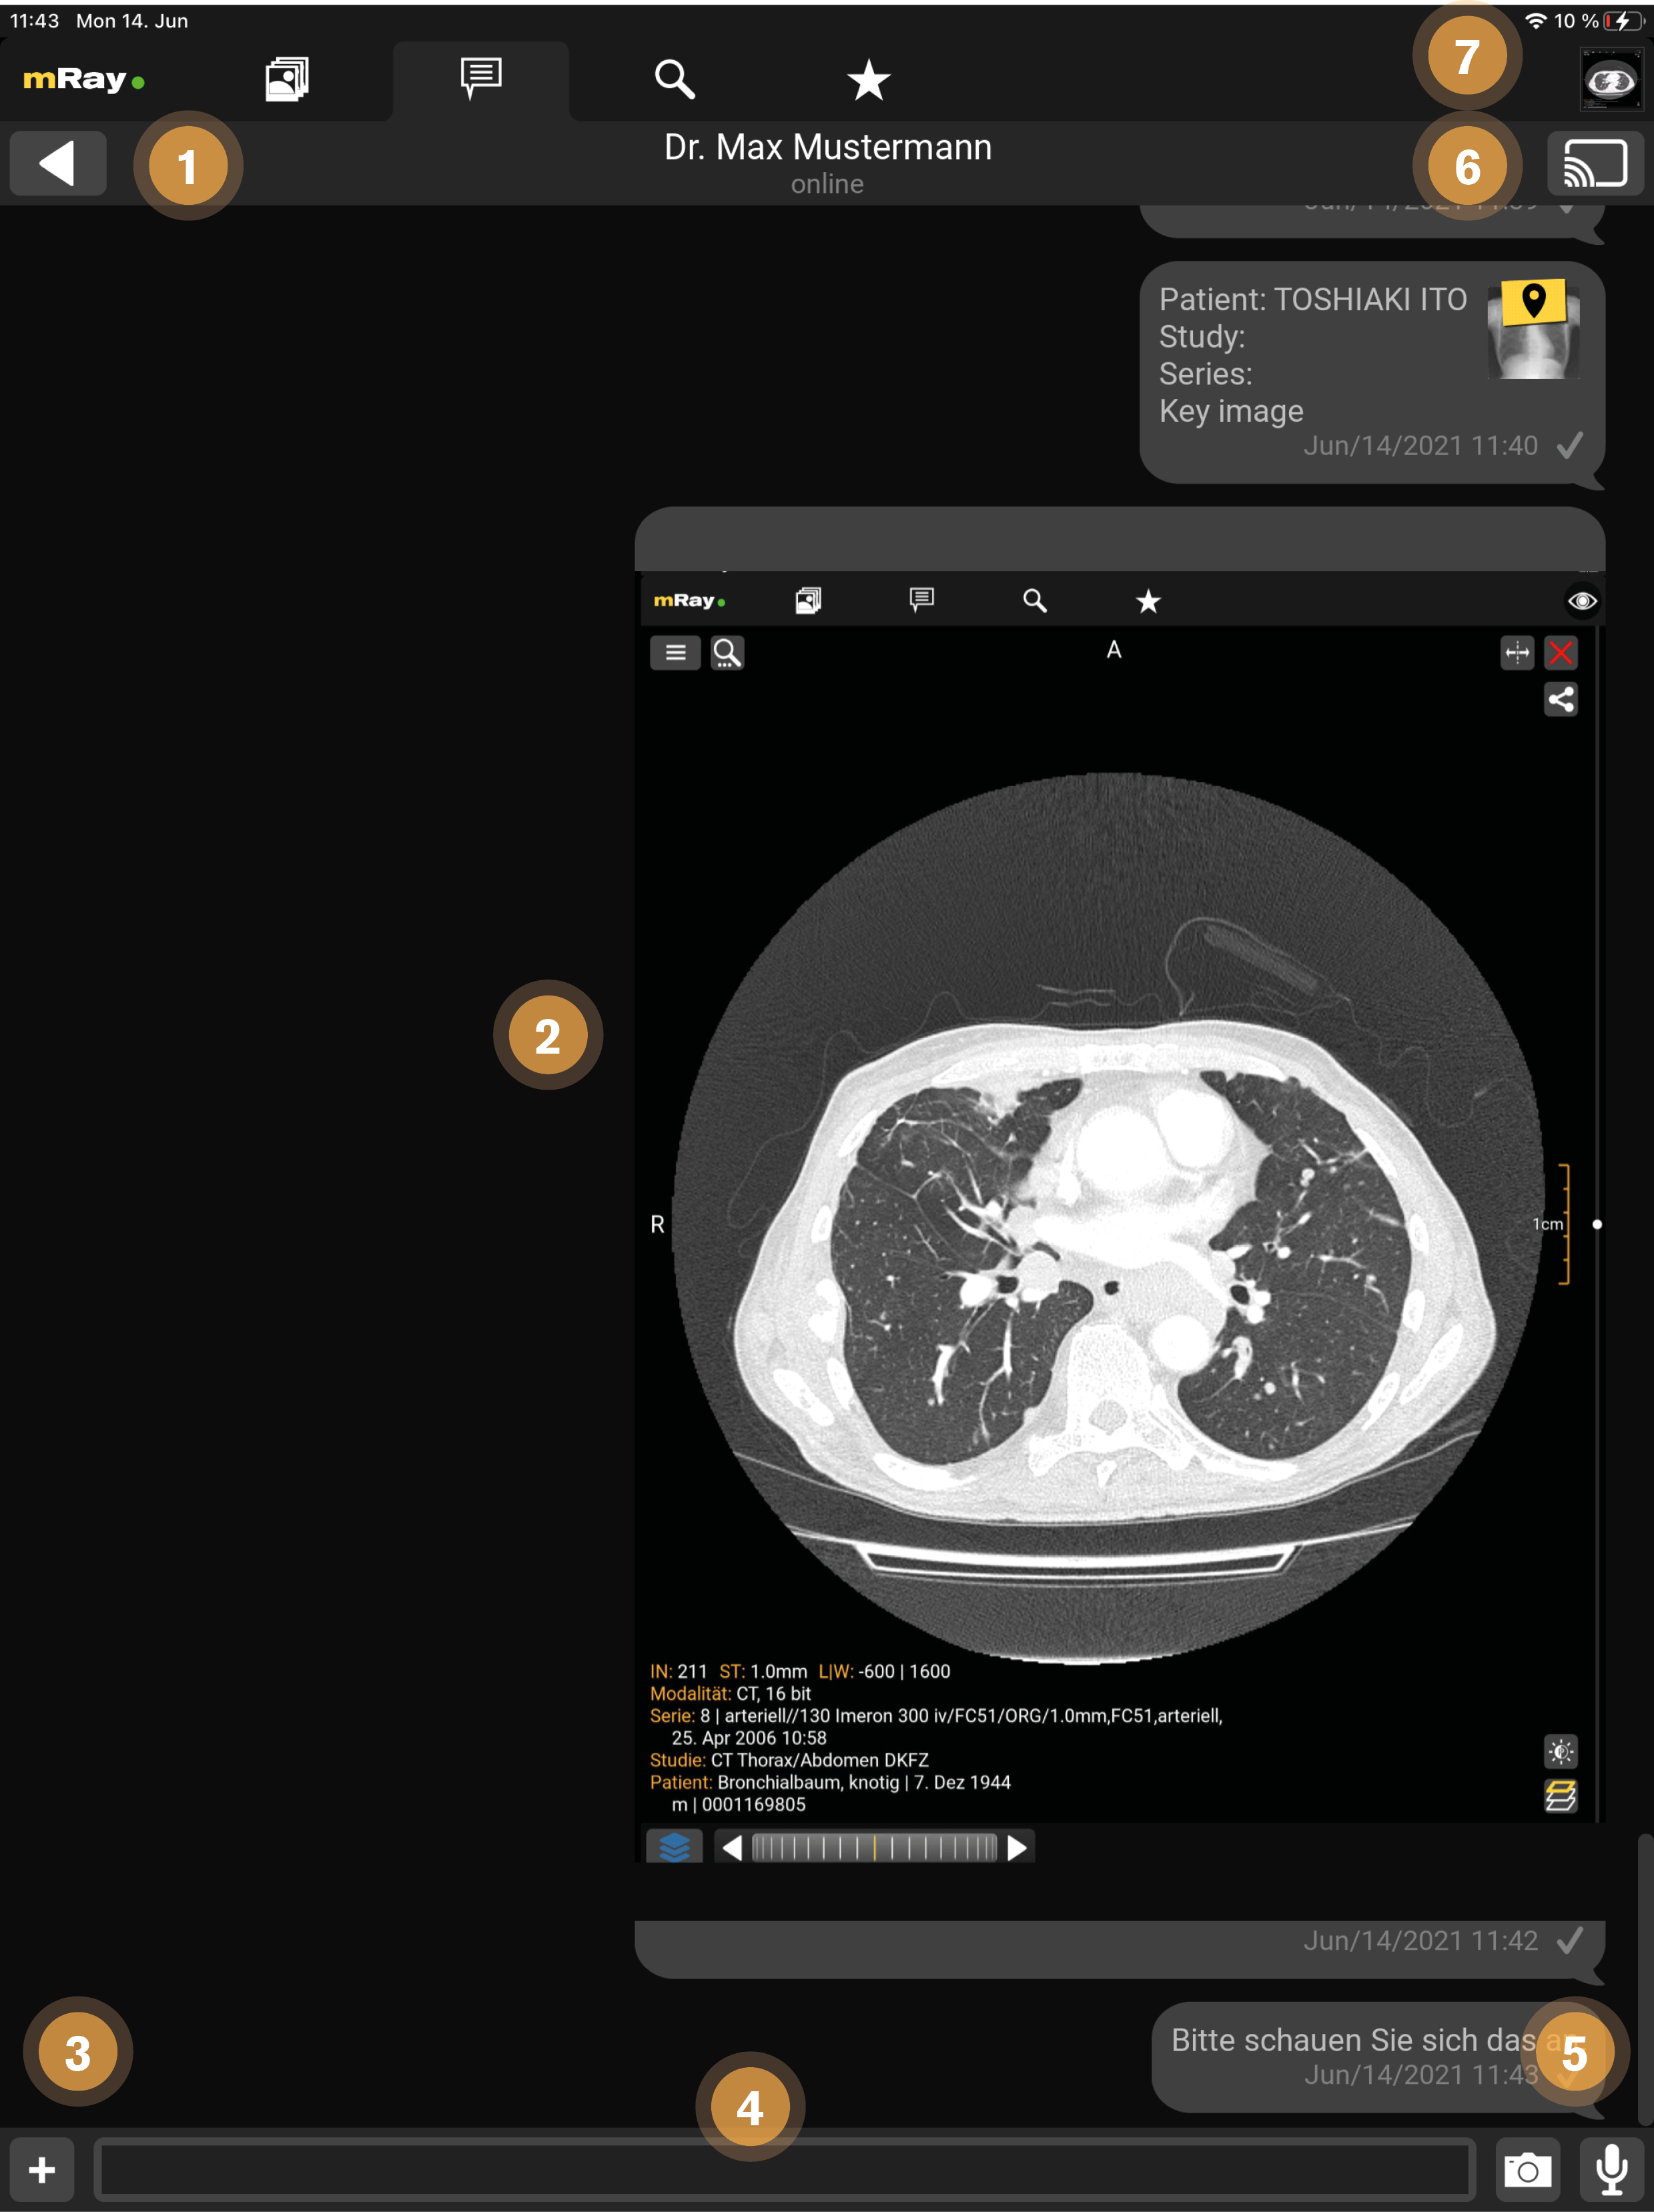

13.1. Chat

Just as known from other messaging applications it is possible to send and receive messages (Chat). Additionally it is possible to share series, key images and sending audio messages.

This screen provides the following functions:

-

Back to the overview.

-

Chat course: Available series and key-images (key icon above the preview image) can be opened by clicking it. Please notice: If you have no access rights for an image a corresponding error message will be displayed.

-

Add an attachment from your phone gallery, which will be send as photo message (see Photo messages)

-

Input field to type your text messages.

-

With the microphone button you can capture audio messages (see chapter Audio messages). With the camera button you can send Photo messages

-

With this button you can start screensharing with all chat participants (see Screensharing).

-

This icon indicates that an image is already open in the background (see Screensharing).